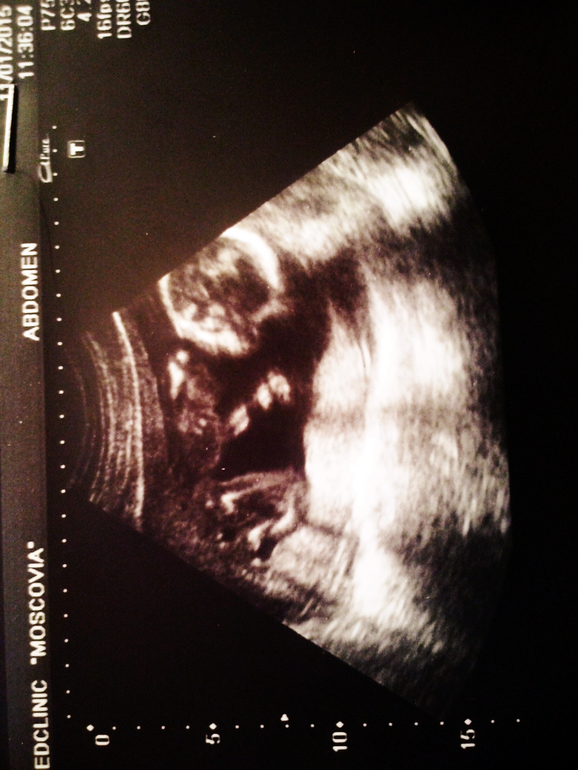

Вопросы про УЗИ, обследования и анализы: что, где, как, когда?Ну вот, интрига раскрыта. Как и предполагал наш замечательный врач Роман Николаевич в наши 13 недель,что мы - Девушка

Да здравствует ВАРВАРА ЕВГЕНЬЕВНА!

Такая хорошенькая, такая подвижная, здоровенькая девочка!

Господи, счастью нет предела. Маленькая моя, всё у нас в норме, развиваемся мы хорошо, даже опережаем срок на недельку, такая хорошенькая, что между ножек показала сразу

а вот когда хотели личико сфотографировать, так она ручкой закрывалась